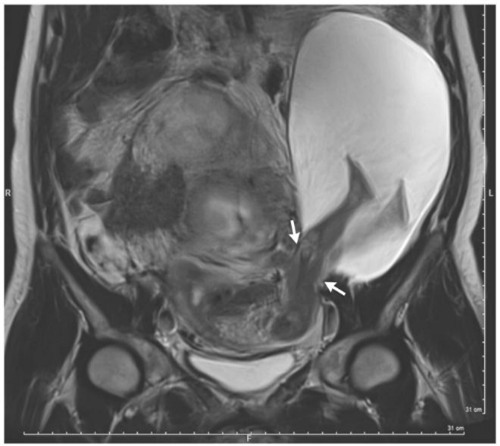

Kết quả chụp phim cũng cho thấy một phần túi ối kích thước 19 x 12 x 9 cm bên trong cơ thể người phụ nữ 33 tuổi đã trượt qua lỗ ở thành tử cung. Kết quả, chân thai nhi đạp ra bên ngoài lớp bảo vệ vốn có.

Đến tuần thứ 30, hình siêu âm cho thấy vết rách đã lớn hơn và thai nhi ngày càng ra ngoài tử cung. Tình hình nghiêm trọng buộc các bác sĩ phải ngay lập tức tiến hành mổ bắt con cho sản phụ. May mắn, em bé chào đời an toàn dù chỉ nặng 1,4 kg. 6 tháng sau ca sinh nở, hai mẹ con đều khỏe mạnh.